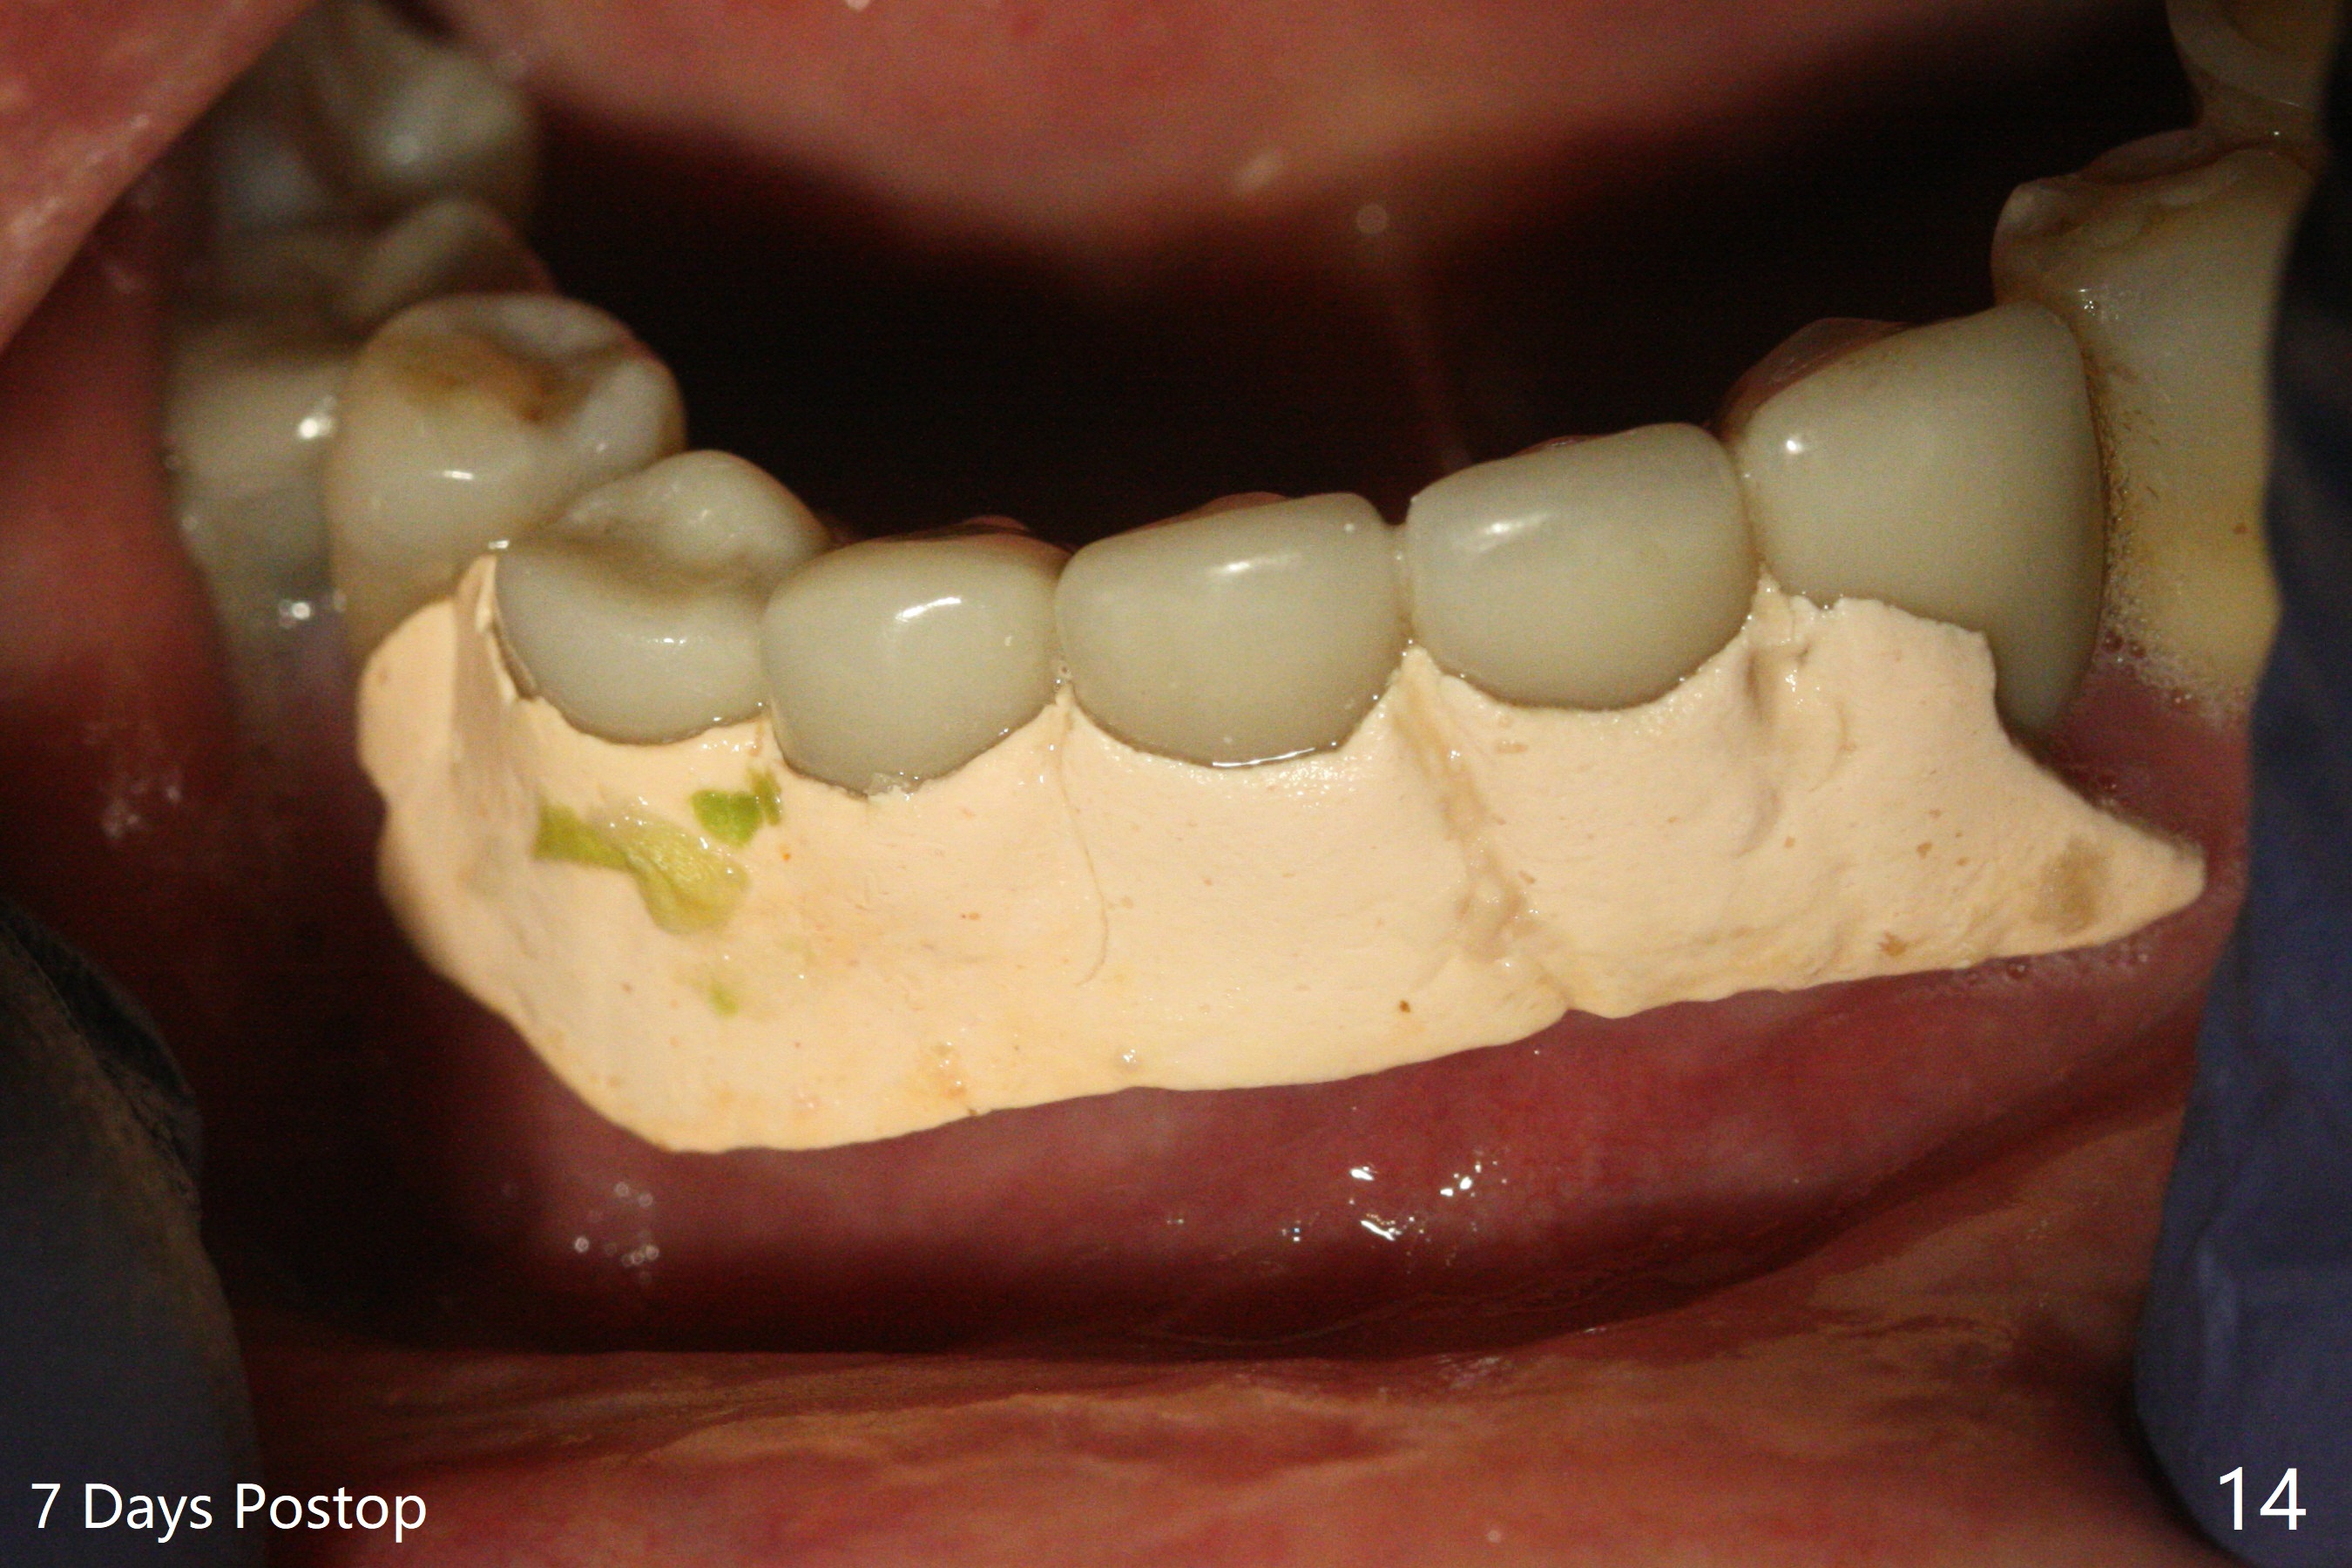

The implants remain asymptomatic years months post cementation (Fig.12), while the one at #27 is associated with buccal and lingual swelling and hemorrhage and bone loss (Fig.13). There is bone loss distal to #27 without symptom 3 years 9 months post cementation (Fig.12). Periimplantitis develops buccal and lingual 4 years 5 months post cementation (coronavirus, Fig.13). Sticky bone and PRF are used after debridement. There is no discomfort 7 days postop (Fig.14,15).